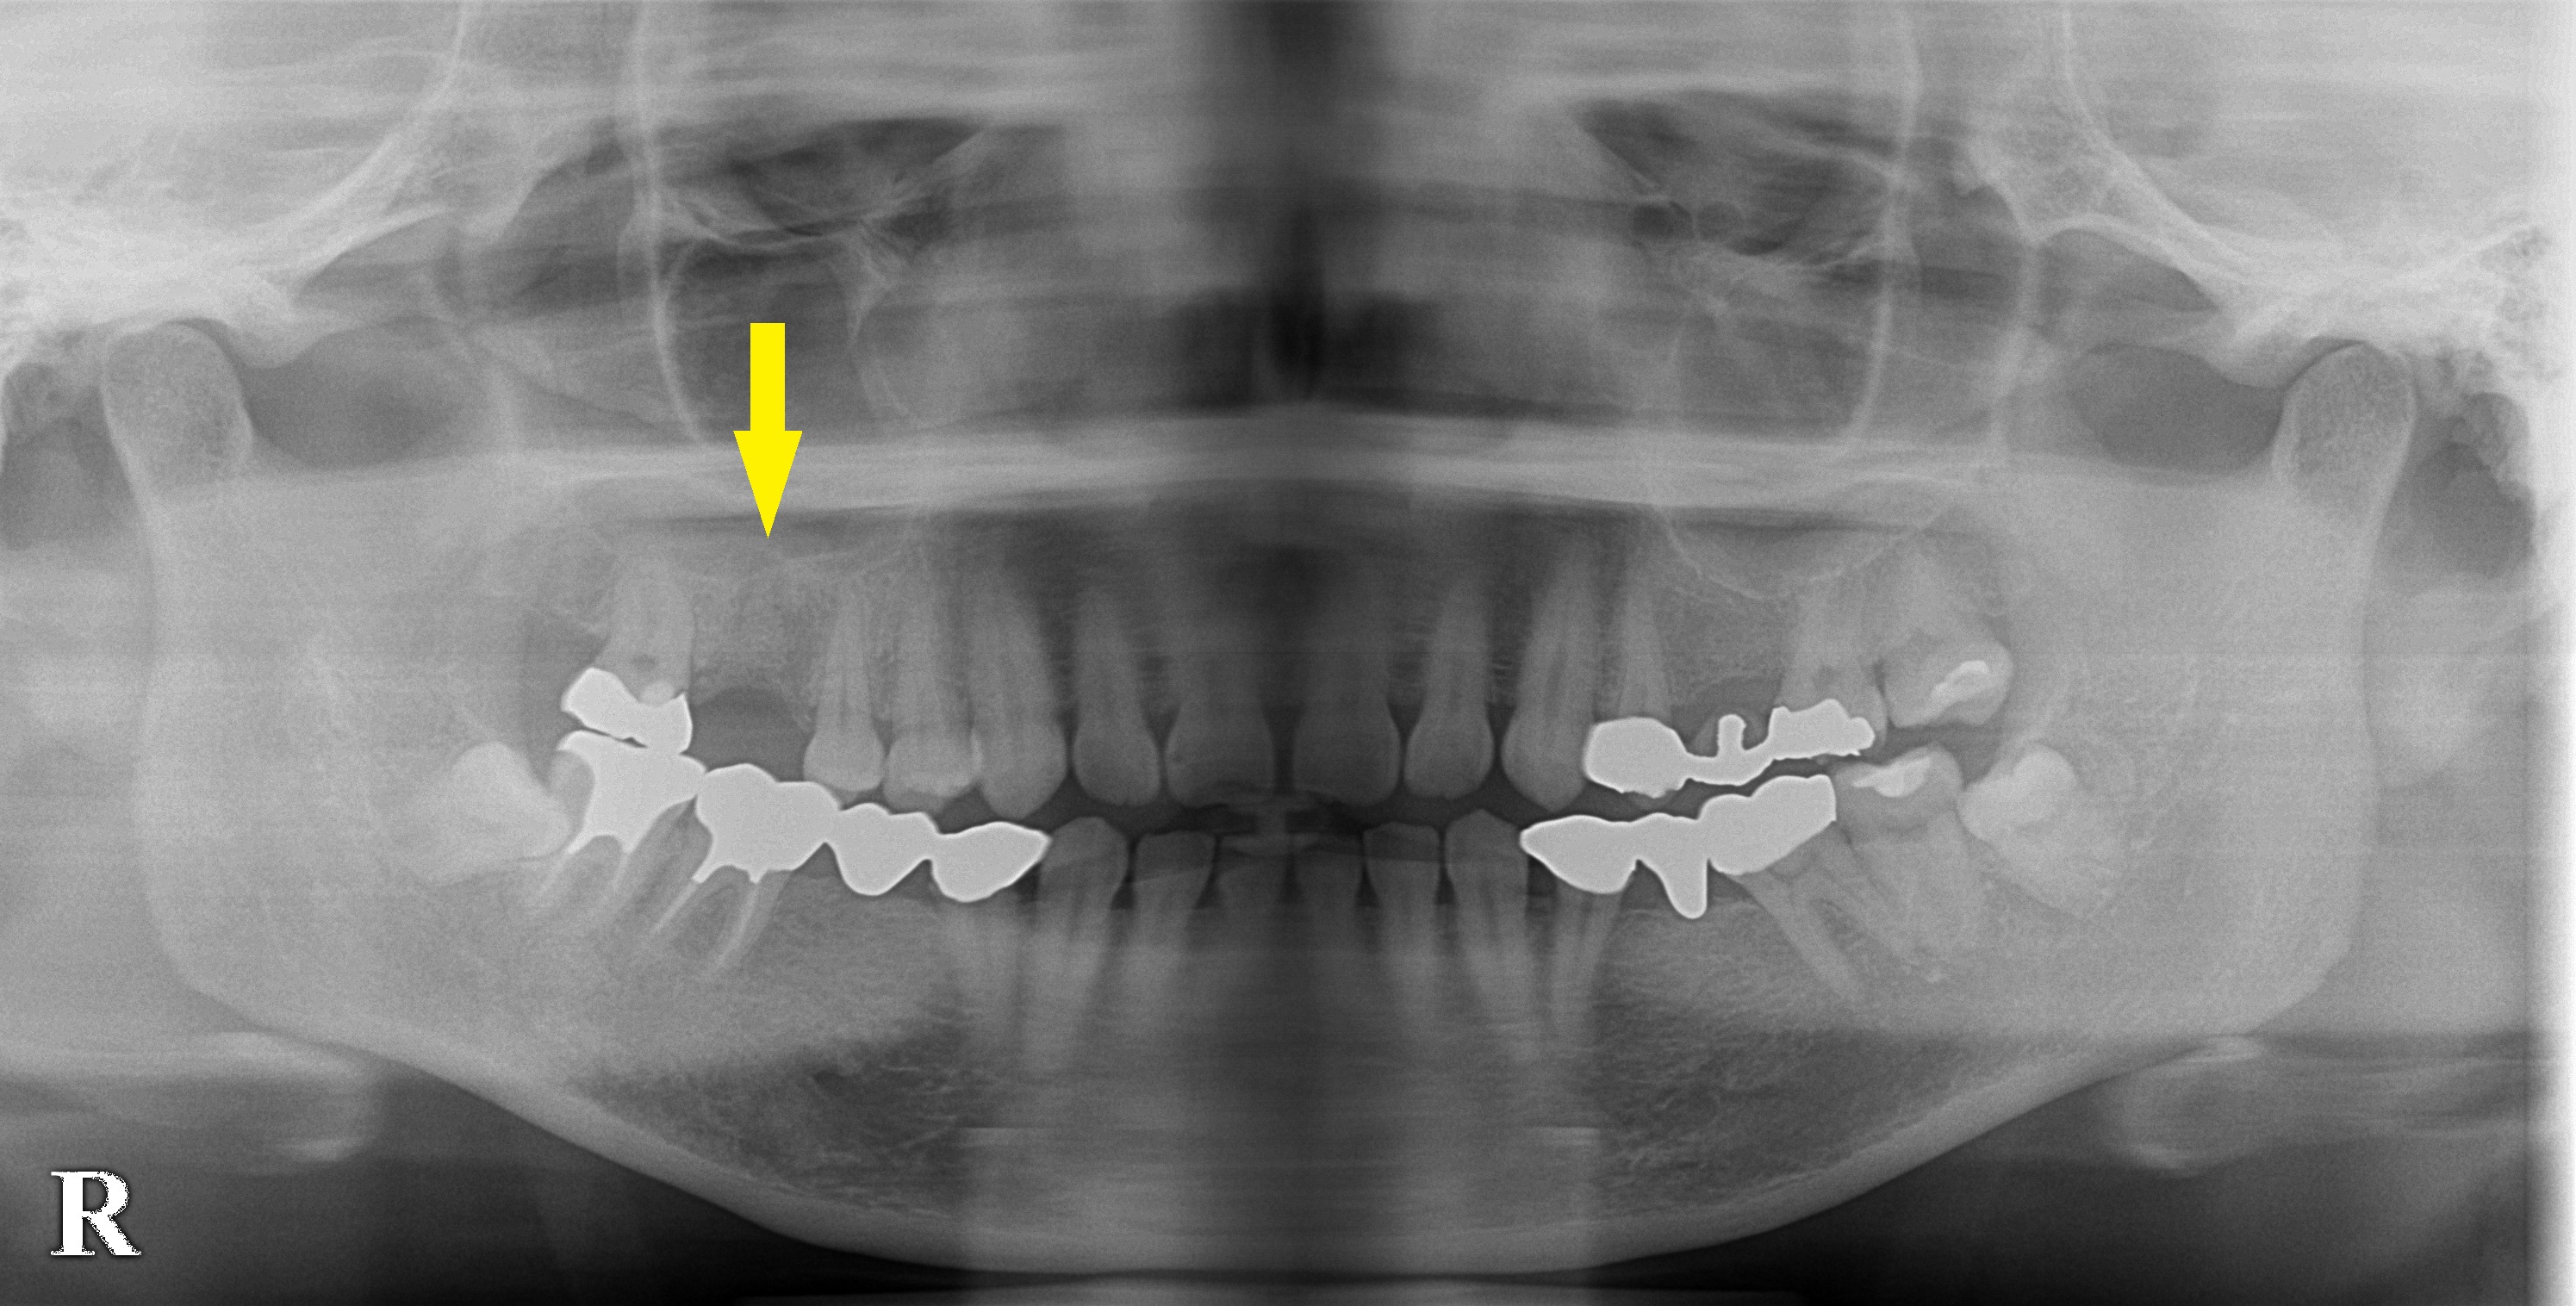

上顎の右側の第一大臼歯が抜歯となり、抜歯していただいた歯科医院で、抜歯した穴に骨補填材を填入されたそうです。

当院でレントゲン、CTを撮影したところ、まだ骨になっていないと思われる材料が残っている状態でした。

CT上で測定すると、これが骨に置き代わったとしても、少し高さが不足すると考えられました。

そこで、骨が成熟するのを数か月待って、ソケットリフトという骨造成術を併用してインプラント埋入を行いました。

下の、1段目が初診時のレントゲン写真、2段目が初診時のCT、3段目がインプラント埋入後のCTです。

ソケットリフトによって、骨がドーム状に造成できました。